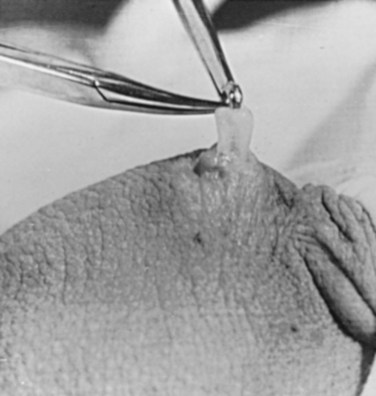

There are several variations to the technique of the no-scalpel vasectomy. One technique involves firmly securing the vas through the skin with a ring-tipped vas deferens fixation clamp (Fig. 37–4) after local anesthesia has been administered as described above (Fig. 37–5). A modified, sharpened tipped curved hemostat (Fig. 37–6) is used to puncture the skin and the vas sheath, and the hemostat is spread to stretch the hole that is made. Then the vas deferens is lifted out, divided, the occlusion technique of choice is employed, inspection is done for hemostasis, and the vas deferens is replaced in the scrotum. The same procedure is performed on the contralateral vas deferens (Huber, 1988). The perforation in the skin can be closed with an absorbable suture, but can also be left open, and will heal well without closure.

Figure 37–4 Ring-tipped vas deferens fixation clamp. Cantilevered design prevents injury.

(From Li S, Goldstein M, Zhu J, Huber D. The no-scalpel vasectomy. J Urol 1991;145:341–4.)

Figure 37–5 Vas fixed in the ring clamp. The scrotal skin is tightly stretched over the most prominent portion of the vas.